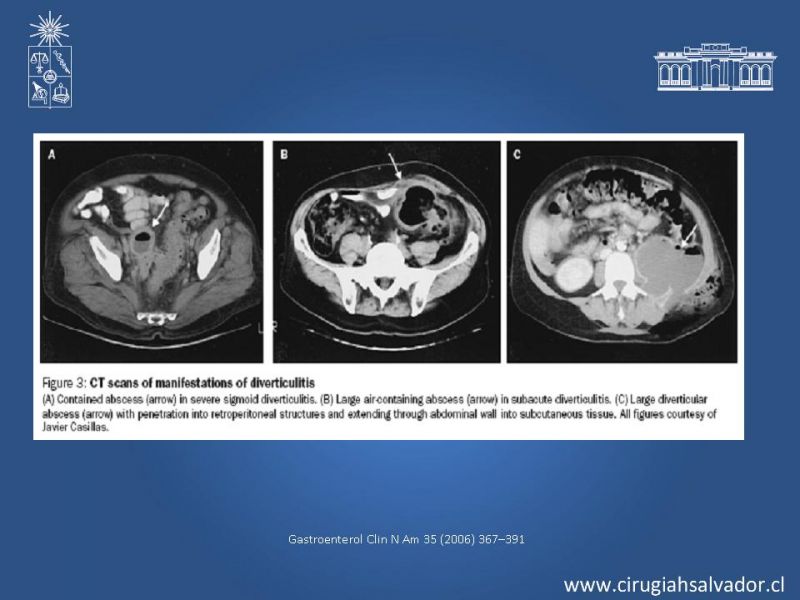

Diverticulitis

Coloproctología